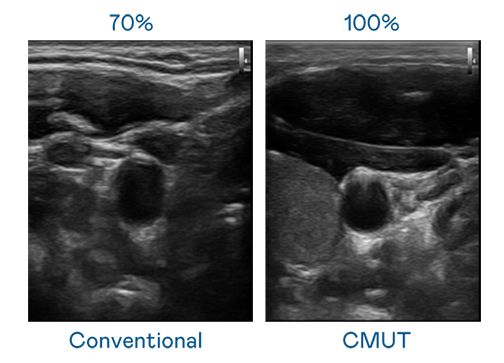

CMUT 技术是一种用电容式微机电元件来产生超音波讯号的技术。与传统 PZT 压电式技术相比,CMUT 频宽增加 30%,更宽频的超音波讯号让影像解析度大幅提升,是实现高影像品质医疗超音波扫描、促进精准医疗发展的关键技术。

大频宽带来超清晰影像

超音波影像的解析度高低,首先取决于探头能发出的讯号频宽。37000a威尼斯 CMUT 可提供高清晰的超音波讯号,提供高频宽、高灵敏度、影像纹理细节更高的超音波影像,协助医护人员缩短影像判读时间及利用精准的医疗影像进行诊断。